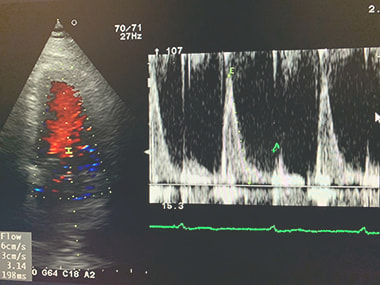

心エコー検査:

心臓が正常に働いているかどうかを調べる検査です。心臓の大きさ、動き、

弁の状態、血液の流れなどを調べ、弁膜症、心筋症、心不全などを診断します。